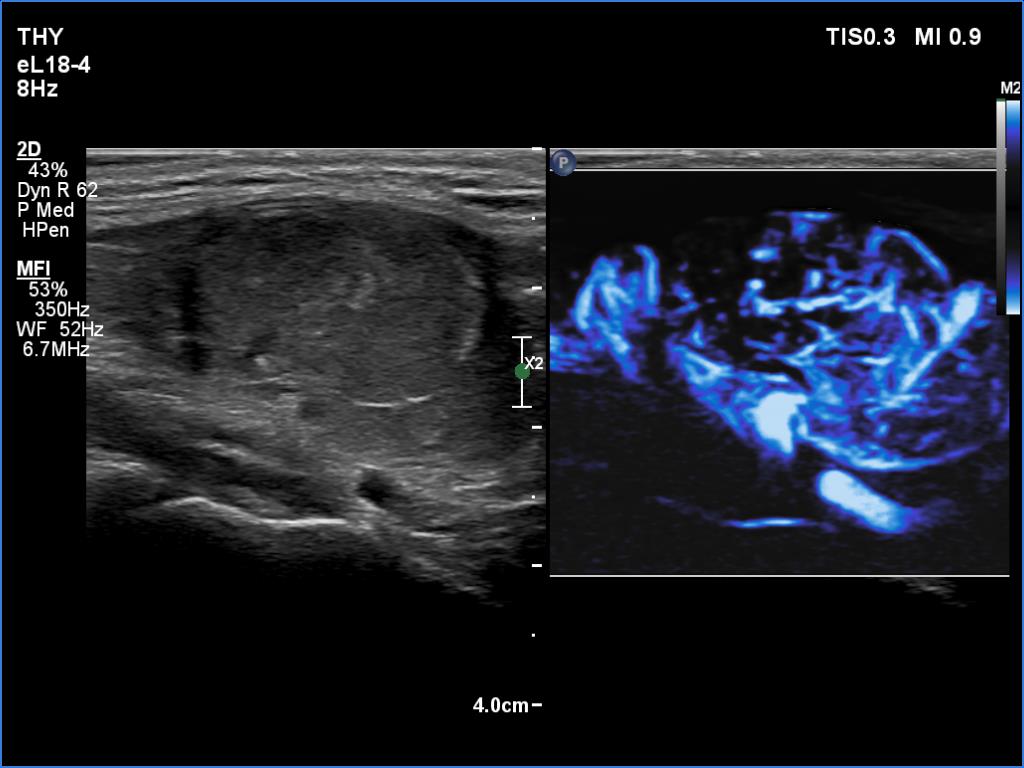

Right lobe, longitudinal scan

Right lobe, longitudinal scan, microflow imaging. The nodule is rich in vessels.